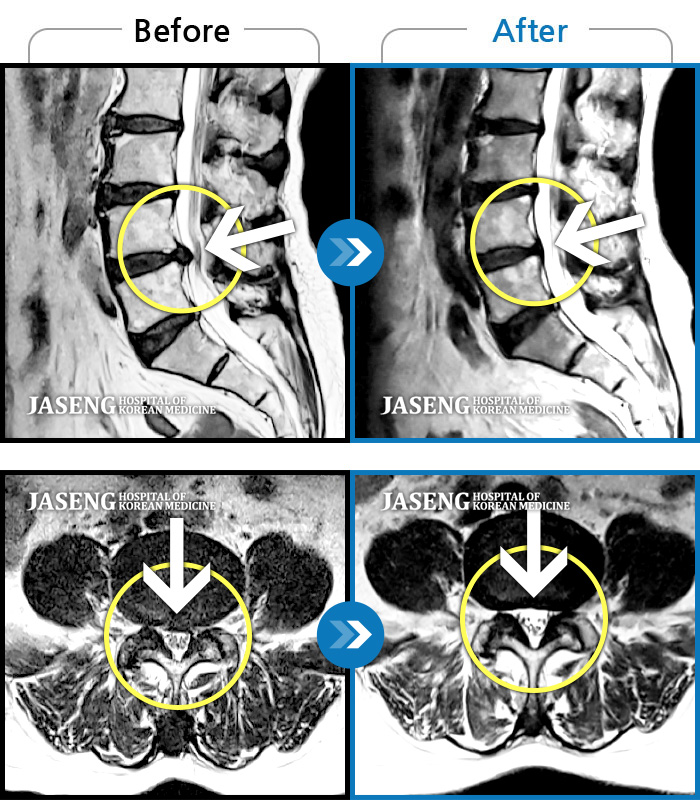

허리디스크 2단계(초기) 진단을 받긴 했으나 다행히 근육량이 많아 모르고 살았는데 사고로 인해 디스크에 상처가 생겨 힘든 나날을 보내고 있습니다

70대 어머니가 디스크파열로 수술을 당장해야한다는 큰병원의 권유를 뒤로하고 자생을 결정하고 엄봉군원장님을 만났습니다. 두달여 치료받고 많이 호전되었고 갈때마다 진심을 다하시는 원장님으로 인해 정서적인 치료도 받고 있답니다 앞으로도 잘 부탁드립니가!!

디스크수술만 두번했어요 사고때문에 생긴 통증때문에 걱정이 많았어요 엄원장님 설명도 알기쉽게 해주시고 환자에대한 배려가 참 많은 분이셔서 많은 도움을 받고있습니다 적절한 치료처방으로 상태도 많이 호전되어 더 신뢰가가고 너무 감사해요 이렇게남아 감사의 글을 드립니다